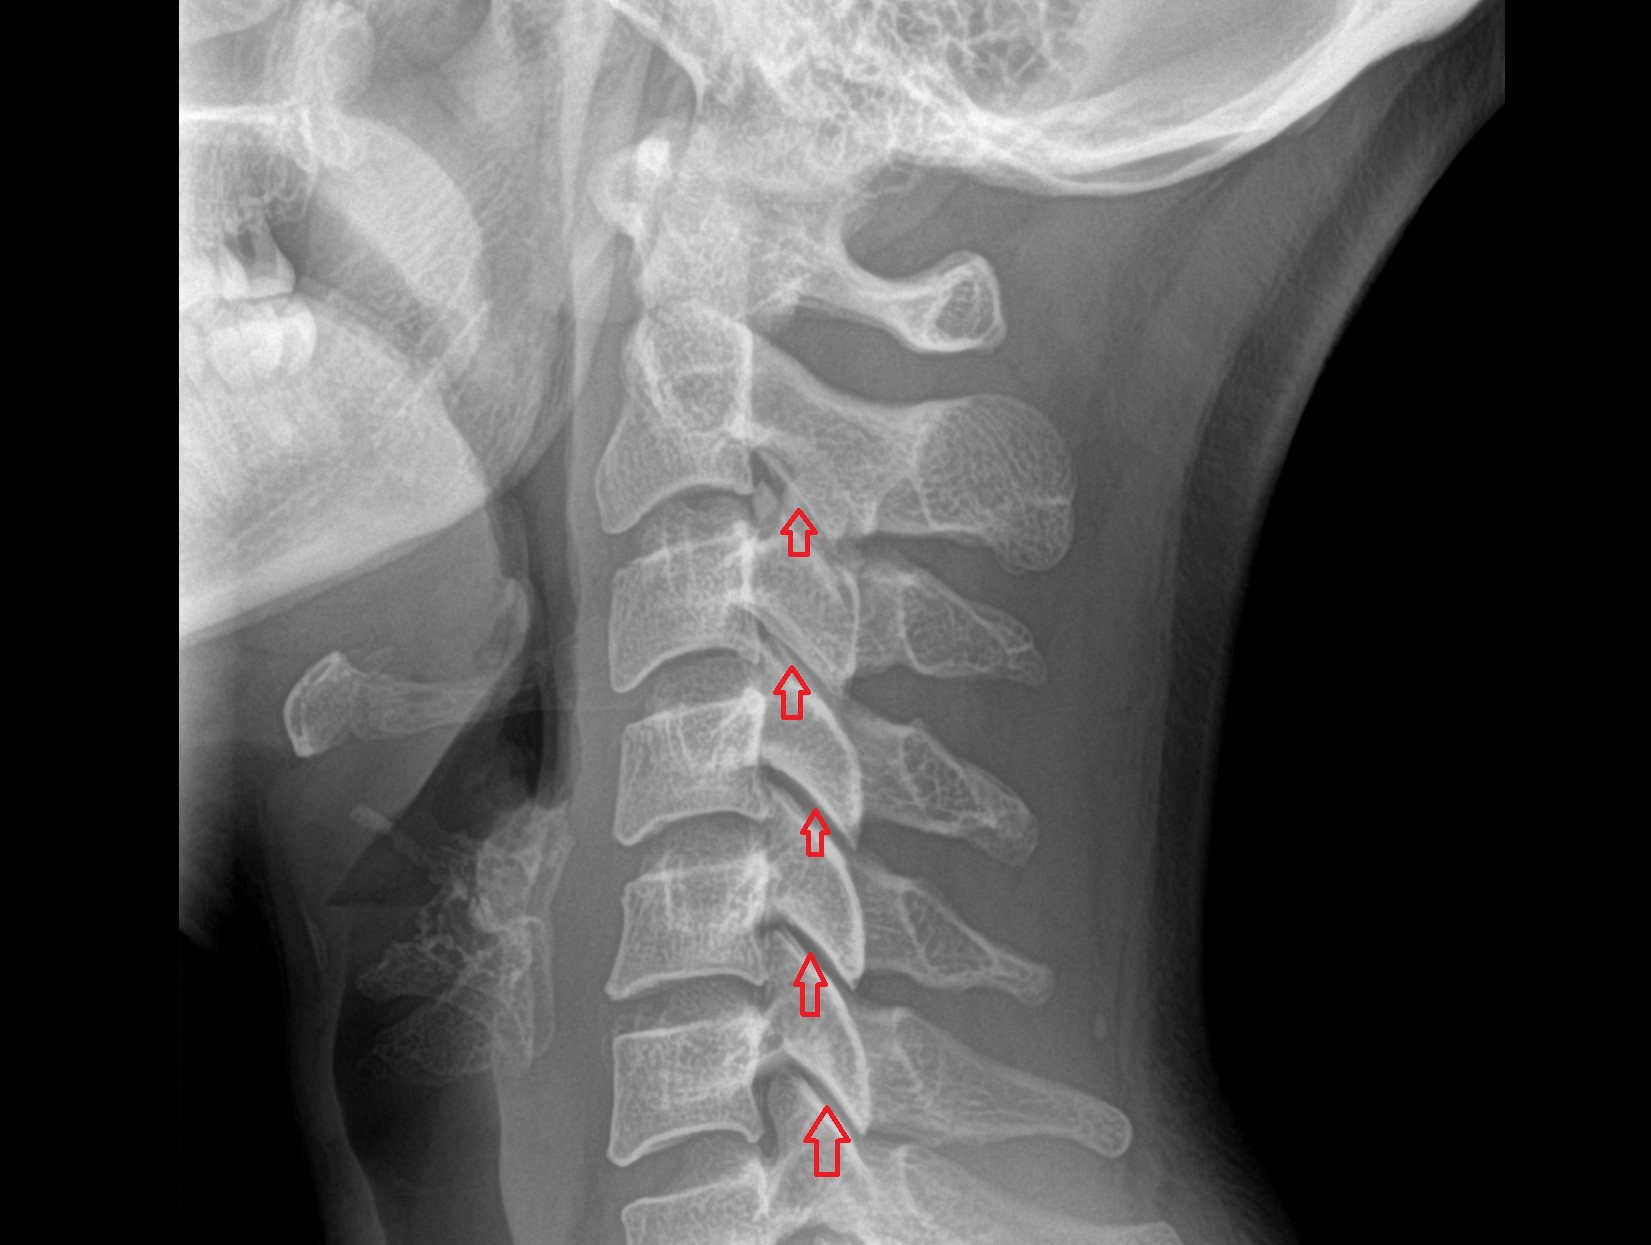

- Facet joint of vertebra (Zygapophyseal joints)

- Anterior longitudinal ligament

- Posterior longitudinal ligament

- Ligamenta flava (Ligamentum flavum)

- Interspinous ligament